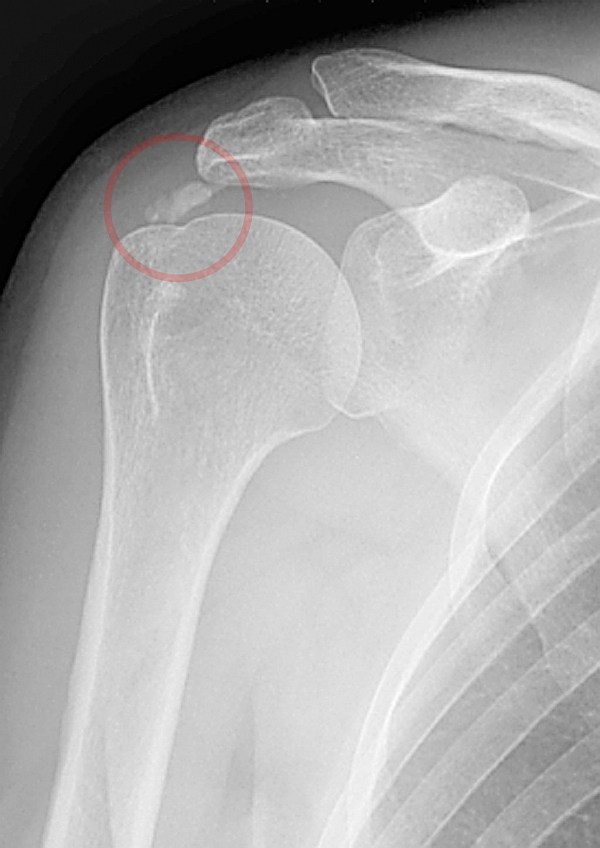

건염의 대표적인 것으로 극상건(supraspinatus)에서 잘 발생하는 석회화 건염(calcific tendinitis), 회전근개에서 잘 발생하는 건염, 그리고 상완골의 외상과 건염, 슬개건염 및 아킬레스 건염 등이 있다. 특히 석회화 건염은 건조직에 석회가 침착하게 되고 이로 인해 통증이 유발되는 질환으로 견관절에서 가장 흔히 발생하며, 회전근개의 석회 침착의 발생 원인에 대해서는 혈액공급의 장애나 고령에 의한 퇴행성 변화, 석회가 흡수되고 재생되는 과정에서 발생하는 섬유연골화생(fibrocartilagenous metaplasia) 등 다양한 가설이 있으나 아직 명확히 밝혀진 바는 없다.

※ 이미지 출처 : http://en.wikipedia.org/wiki/Calcific_tendinitis